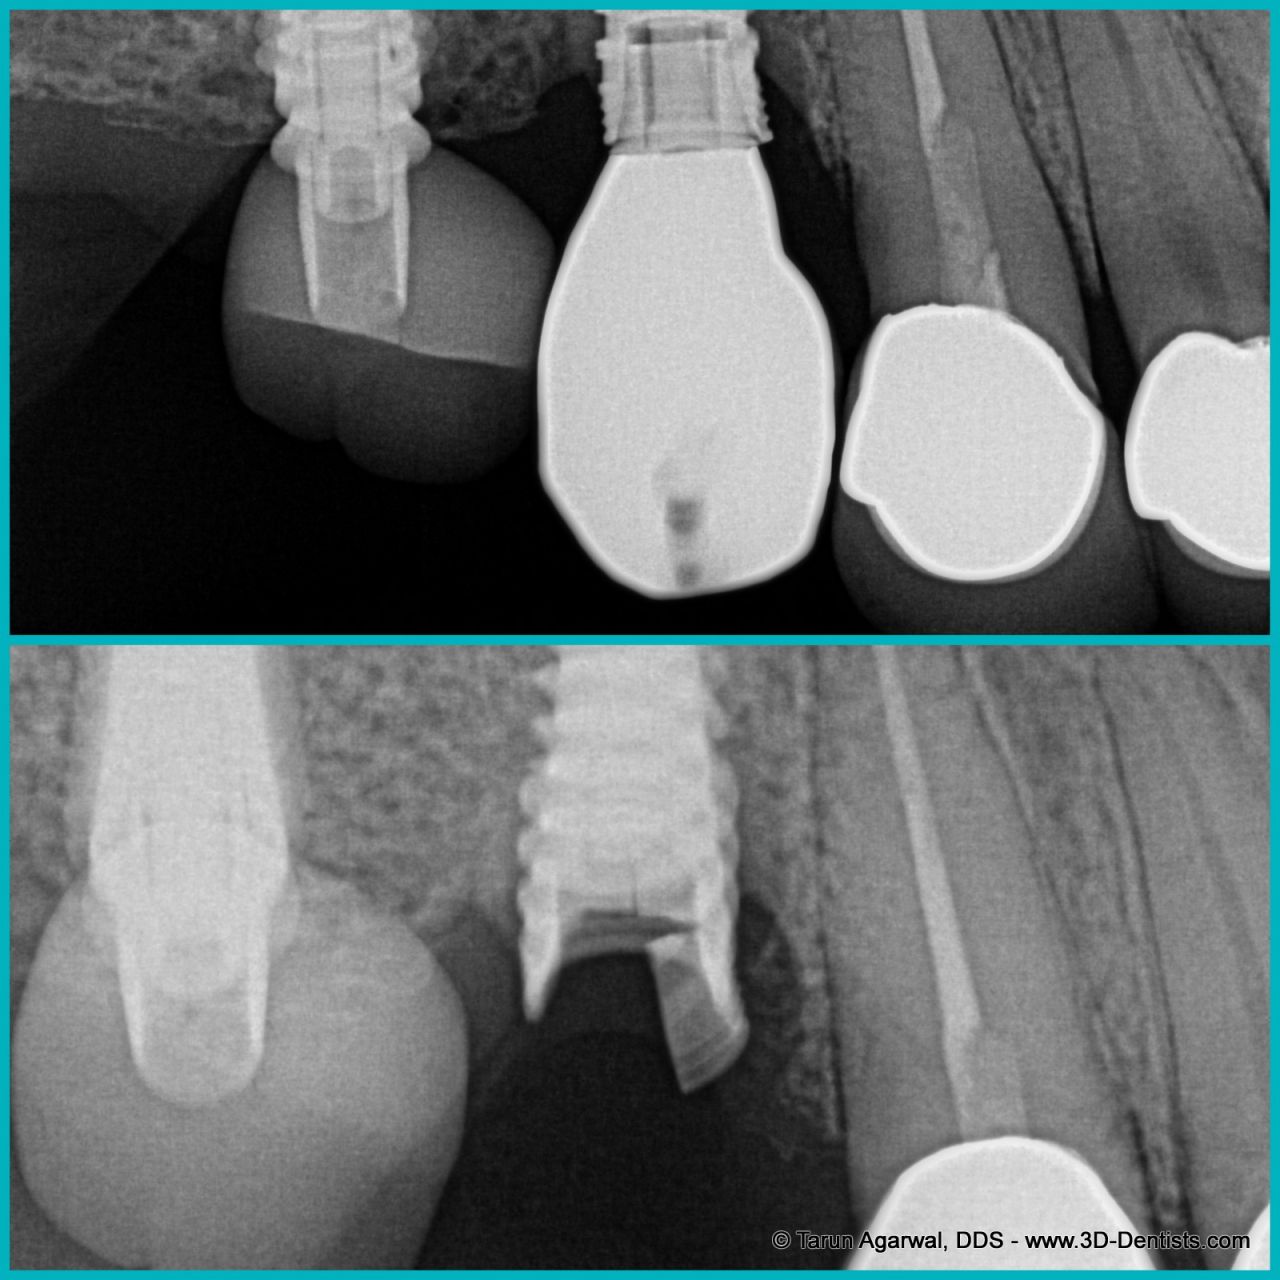

The image below shows 2 situations; the upper image shows an intact dental implant in the middle of the frame, with a broken temporary acrylic crown on the very left side of the picture.

The lower image shows a new temporary acrylic crown on the left-side tooth, but the dental implant in the center of the picture is now cracked. It must be removed.

Broken dental implant X rayImage courtesy Dr. Tarun Agarwal DDS